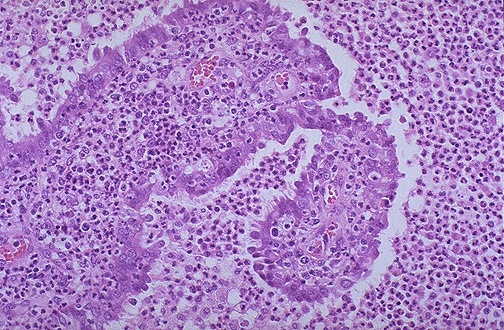

A remnant of tubal epithelium is seen here surrounded and infiltrated by numerous neutrophils. This is acute salpingitis. Neisseria gonorrheae was cultured.